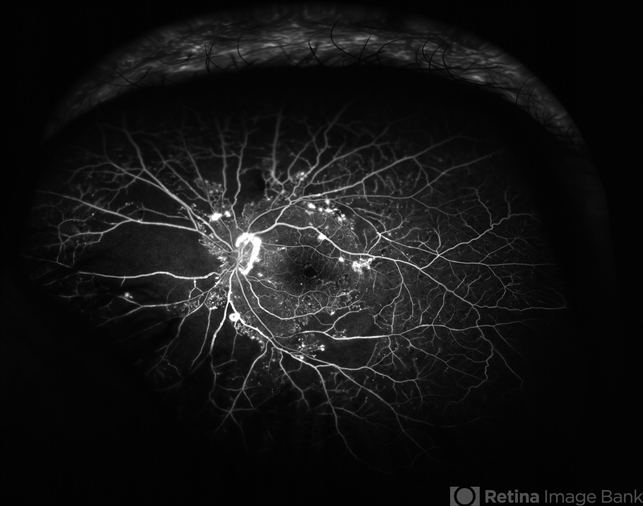

Optos angiography is useful for imaging peripheral ischemia.

- Fluorescein angiogram of the left eye of a 65 year old woman with diabetes mellitus showing nasal peripheral retinal capillary dropout and neovascularization of the disc. Scattered retinal microaneurysms are also noted